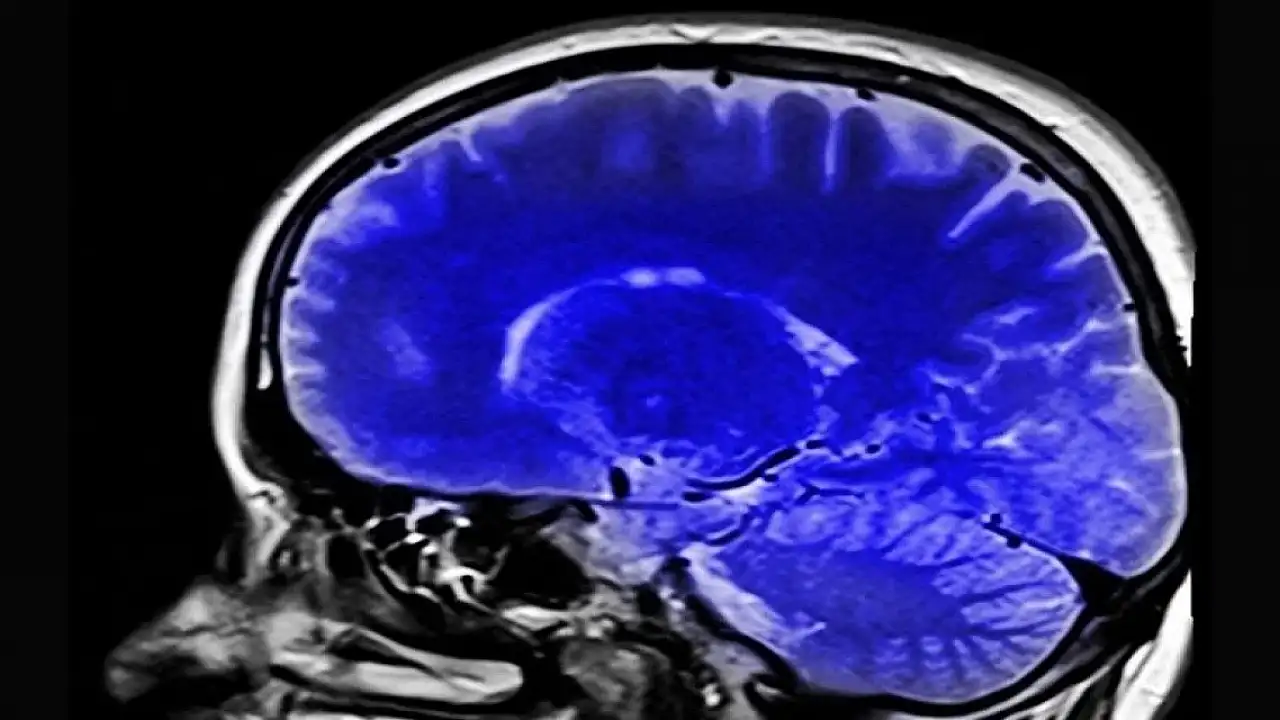

Araştırmacılar, katılımcıların kronik ağrı düzeylerine bağlı olarak tepkilerinin yansıdığı düşünülen beynin "anterior singulat korteks (ACC)" ve "orbitofrontal korteks (OFC)" adlı iki bölgesindeki aktivite değişikliklerine odaklandı.

Shirvalkar, akut ağrılar tecrübe edildiğinde MR taramalarıyla beynin ACC ve OFC bölgelerindeki yansımalarını görebildiklerini belirterek, buradan yola çıkarak beyindeki ACC ve OFC bölgelerinin kronik ağrı oluştuğunda nasıl tepki verecekleriyle ilgilendiklerini kaydetti.